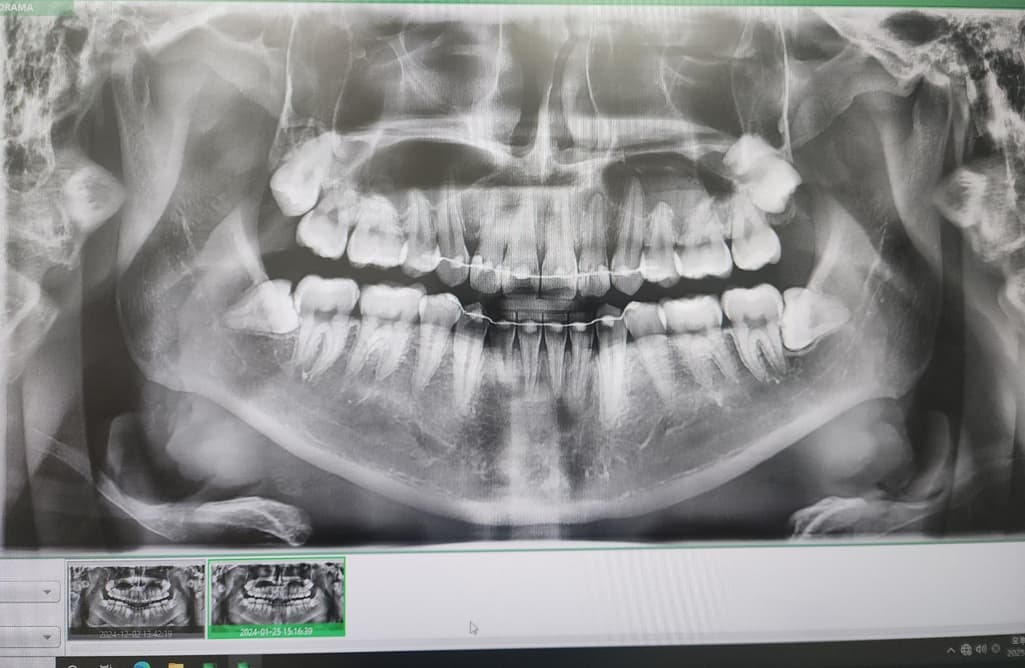

사진은 24년1월 24년 12월 25년 5월 순입니다

• 2번 째 사진

사진상으로는 염증이 명백히 보이지만 증상이 없다면 일단 지켜보는 것도 괜찮을 것 같습니다.

엑스레이 상으로는 크게 염증이 커지거나 그렇진 않은거 같습니다. 증상이 없다면 정기적으로 치과를 다니시면서 관리를 받으시면될것같습니다.

파노라마 사진상으로 측은단 부위에 병소가 보이고 있습니다. 정확한 확인을 위해서는 CT 촬영을 해보는 것이 좋을 것으로 생각되며 치근단 질환이 생겼다는 것은 근관 내가 이미 감염이 되었다는 것이기 때문에 치근단 질환이 있다면 신경 치료를 해줘야 합니다. 그렇지 않다면 주변에 있는 치조골이 손상되어 나중에는 치아를 손실 할 수도 있습니다.